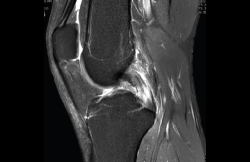

1.2.2. Ligamento cruzado anterior (LCA) (Figuras 40, 41, 42, 43 y 44)

Figura 40. Corte de secuencia sagital T2 Fat-Sat de resonancia magnética de rodilla: ligamento cruzado anterior normal.

Figura 41. Cortes de secuencia sagital T2 Fat-Sat de resonancia magnética de rodilla: rotura central del ligamento cruzado anterior.

Figura 42. Cortes de secuencia sagital T2 Fat-Sat: rotura proximal del ligamento cruzado anterior.